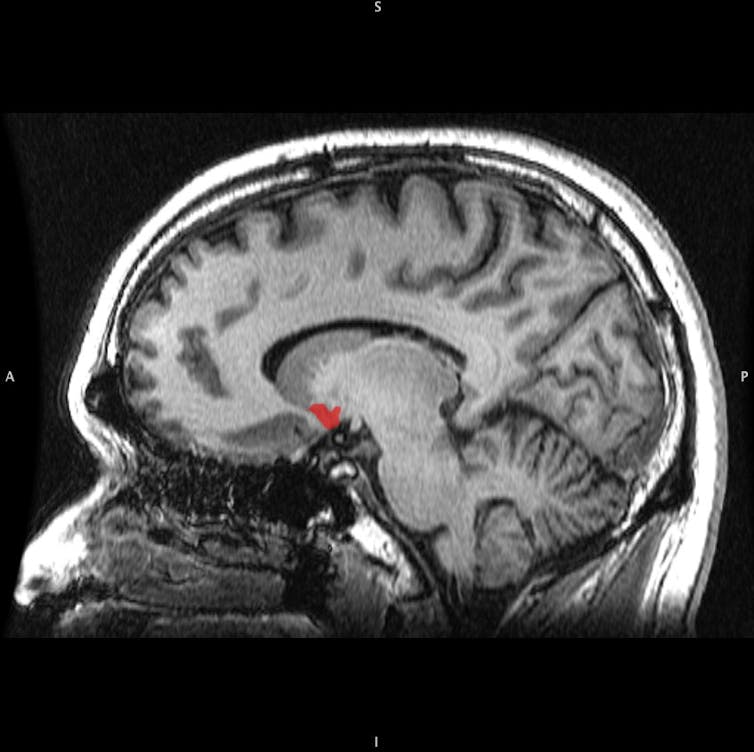

The nucleus accumbens. Geoff B Hall

Evolution has resulted in the mesolimbic pathway, a brain system that deciphers these natural rewards for us. When we do something pleasurable, a bundle of neurons called the ventral tegmental area uses the neurotransmitter dopamine to signal to a part of the brain called the nucleus accumbens. The connection between the nucleus accumbens and our prefrontal cortex dictates our motor movement, such as deciding whether or not to taking another bite of that delicious chocolate cake. The prefrontal cortex also activates hormones that tell our body: “Hey, this cake is really good. And I’m going to remember that for the future.”